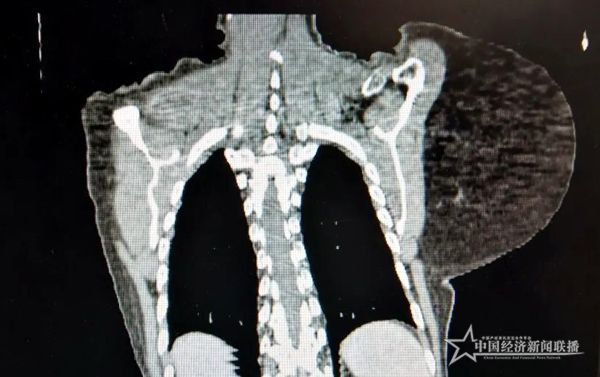

患者在長期重壓下,脊柱已經(jīng)側(cè)彎

因?yàn)槟[瘤特別大,而且靠近頸部和脊椎,血管神經(jīng)繁多,且老人合并有多種內(nèi)科疾病,經(jīng)過討論,精心為其制定了最佳手術(shù)方案。做足術(shù)前準(zhǔn)備后,該院頸胸心血管外科團(tuán)隊(duì)順利為其施行肩甲部大腫瘤切除術(shù),完整切除約5斤重腫瘤,幫助患者回歸健康人生。